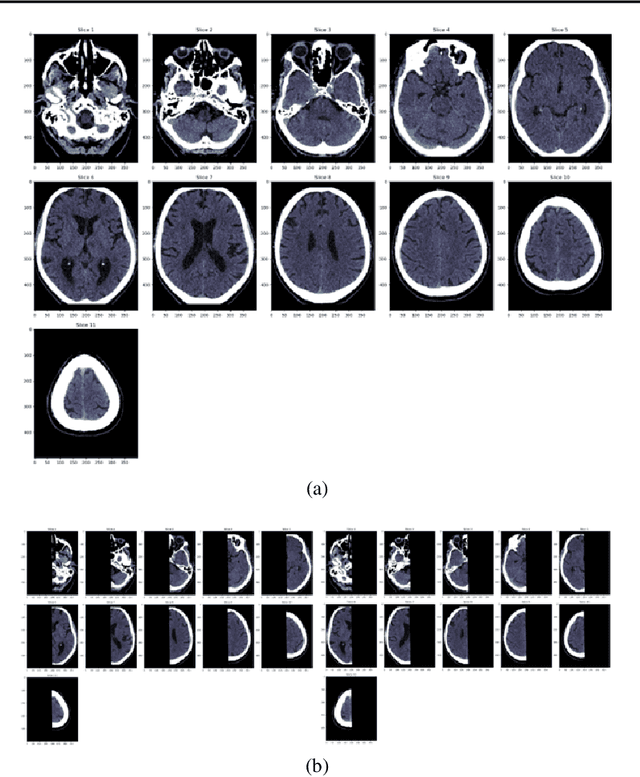

Abstract:Despite the large amount of brain CT data generated in clinical practice, the availability of CT datasets for deep learning (DL) research is currently limited. Furthermore, the data can be insufficiently or improperly prepared for machine learning and thus lead to spurious and irreproducible analyses. This lack of access to comprehensive and diverse datasets poses a significant challenge for the development of DL algorithms. In this work, we propose a complete semi-automatic pipeline to address the challenges of preparing a clinical brain CT dataset for DL analysis and describe the process of standardising this heterogeneous dataset. Challenges include handling image sets with different orientations (axial, sagittal, coronal), different image types (to view soft tissues or bones) and dimensions, and removing redundant background. The final pipeline was able to process 5,868/10,659 (45%) CT image datasets. Reasons for rejection include non-axial data (n=1,920), bone reformats (n=687), separated skull base/vault images (n=1,226), and registration failures (n=465). Further format adjustments, including image cropping, resizing and scaling are also needed for DL processing. Of the axial scans that were not localisers, bone reformats or split brains, 5,868/6,333 (93%) were accepted, while the remaining 465 failed the registration process. Appropriate preparation of medical imaging datasets for DL is a costly and time-intensive process.